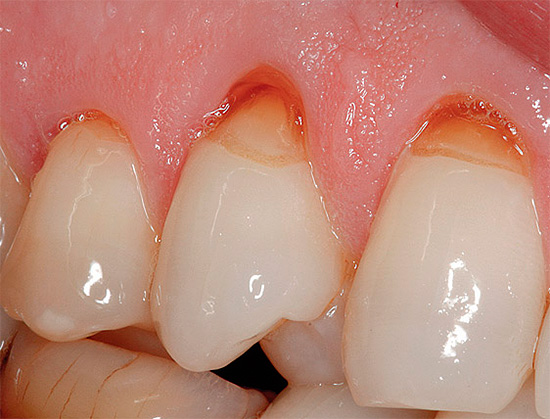

Fotografia cárie primária na área cervical do dente:

Abaixo está uma foto de cárie cervical no estágio local:

Nas cáries superficiais, a dor geralmente ocorre por irritantes químicos (salgados, doces) e pela temperatura (frio). Externamente, nesta fase, a doença se assemelha à cárie no local da mancha, mas ao sondar um dentista com um instrumento afiado especial (sonda), uma zona de rugosidade é detectada no centro do local vasto.